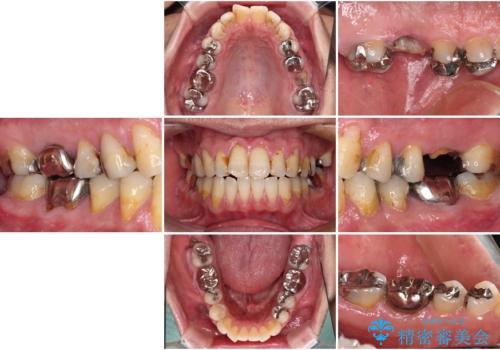

欠損と痛み 奥歯のむし歯治療

- 根っこの一部だけになった歯と咬むと痛みのある歯を気にして来院された患者様です。

上顎の歯根のみとなった歯は抜歯が必要であったので、抜歯を行い、インプラントあるいはブリッジのよる補綴治療を提案しました。

前後の歯は銀歯が装着されていたため、ブリッジによる補綴治療として、前後の歯もセラミックに置き換えることとしました。

下顎の根管治療がされた大臼歯は咬合時に痛みが認められたため、再度根管治療を行った後に補綴治療することとしました。

歯根のみとなっていた上顎の歯は、そのうち治療すれば残せるであろうと思っていたようですが、どこの歯医者に相談しても抜歯と言われたため、抜歯することとしたようです。

むし歯は放置して改善することはあり得ませんので、早めの処置が大切です。